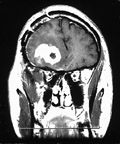

Λονδίνο: Νέα ερευνητικά στοιχεία έρχονται να ενισχύσουν τη θεωρία ότι το κακοήθες γλοίωμα προκαλείται όταν βλαστοκύτταρα εντός του εγκεφάλου αρχίζουν να πολλαπλασιάζονται μη φυσιολογικά, σύμφωνα με δημοσίευμα του επιστημονικού εντύπου Neuron.